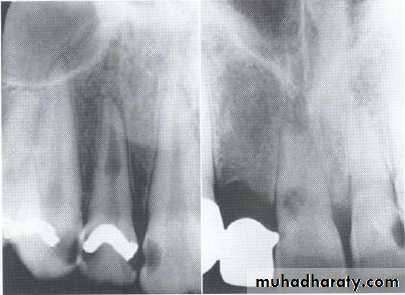

• Fusion of the left mandibular central and lateral incisors (twoindividual roots, two root canals and two joined crowns).

Gemination of right mandibular central incisor has one root, one root canal and a partially bifid dental crown.